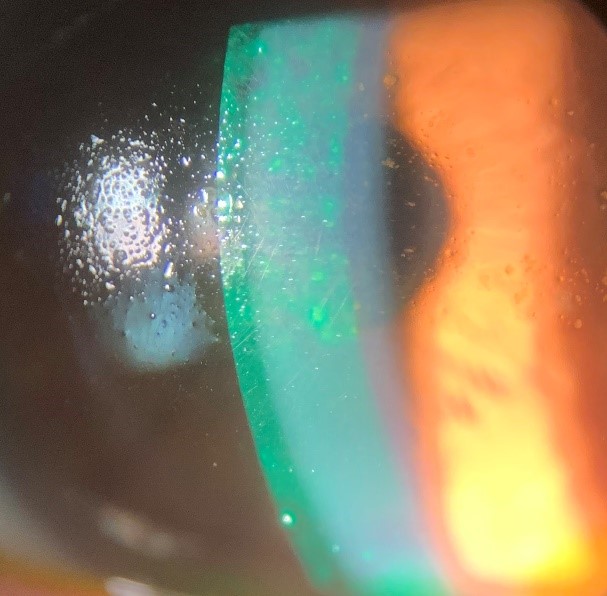

Scleral Contact Lenses Cloudy . If you are reading this article, you are probably experiencing these symptoms and seek a fix. Depending on the frequency and severity of symptoms, several causes can contribute to this pathology. Unfortunately, about 30% of patients with scleral lenses may experience lens fogging. If you insert your lens and it stings or looks cloudy, there could be makeup or other residues on the lens. During examination, patients might complain of clouding, fogginess or blurry vision which oftentimes can be attributed to midday fogging (mdf). Fine, white diffuse particles in the fluid reservoir. Even the best fitting scleral lenses will not feel good if they are not cleaned and cared for properly. Remove your lens, rinse, and reinsert. 2 mucins and lipids are attracted to the hydrophobic oxygen permeable scleral lens material, forming deposits and resulting in poor wettability. This requires them to remove their lenses and refresh the saline solution, that keeps their. Scleral contact lenses can restore vision for keratoconus and other conditions where the front eye surface is not smooth. Follow the recommendations of your practitioner for your cleaning products and routine. Landing on the sclera (the white part of the eye), scleral lenses can completely transform a highly irregular corneal shape and surface.

Unfortunately, about 30% of patients with scleral lenses may experience lens fogging. Depending on the frequency and severity of symptoms, several causes can contribute to this pathology. Scleral contact lenses can restore vision for keratoconus and other conditions where the front eye surface is not smooth. Fine, white diffuse particles in the fluid reservoir. If you are reading this article, you are probably experiencing these symptoms and seek a fix. 2 mucins and lipids are attracted to the hydrophobic oxygen permeable scleral lens material, forming deposits and resulting in poor wettability. This requires them to remove their lenses and refresh the saline solution, that keeps their. During examination, patients might complain of clouding, fogginess or blurry vision which oftentimes can be attributed to midday fogging (mdf). If you insert your lens and it stings or looks cloudy, there could be makeup or other residues on the lens. Follow the recommendations of your practitioner for your cleaning products and routine.

Scleral Contact Lenses Cloudy Depending on the frequency and severity of symptoms, several causes can contribute to this pathology. Even the best fitting scleral lenses will not feel good if they are not cleaned and cared for properly. Unfortunately, about 30% of patients with scleral lenses may experience lens fogging. This requires them to remove their lenses and refresh the saline solution, that keeps their. Landing on the sclera (the white part of the eye), scleral lenses can completely transform a highly irregular corneal shape and surface. Remove your lens, rinse, and reinsert. Follow the recommendations of your practitioner for your cleaning products and routine. During examination, patients might complain of clouding, fogginess or blurry vision which oftentimes can be attributed to midday fogging (mdf). If you insert your lens and it stings or looks cloudy, there could be makeup or other residues on the lens. If you are reading this article, you are probably experiencing these symptoms and seek a fix. 2 mucins and lipids are attracted to the hydrophobic oxygen permeable scleral lens material, forming deposits and resulting in poor wettability. Depending on the frequency and severity of symptoms, several causes can contribute to this pathology. Fine, white diffuse particles in the fluid reservoir. Scleral contact lenses can restore vision for keratoconus and other conditions where the front eye surface is not smooth.